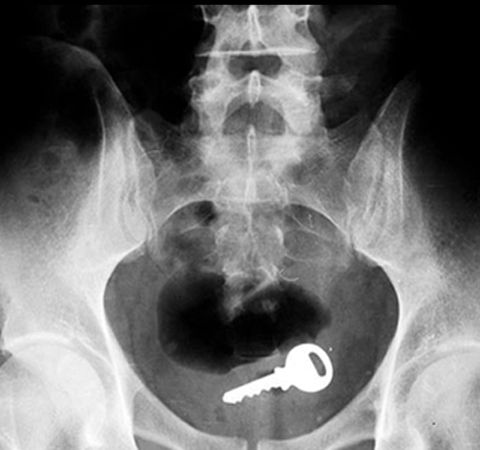

友人の看護師が送信してきたX線画像がテラオソロシイ。

カギ。

救急救命室で働いてた頃、年に10~20人はこの手の患者が来た。

ビンやらスプーンやらなんでもかんでもって感じ。